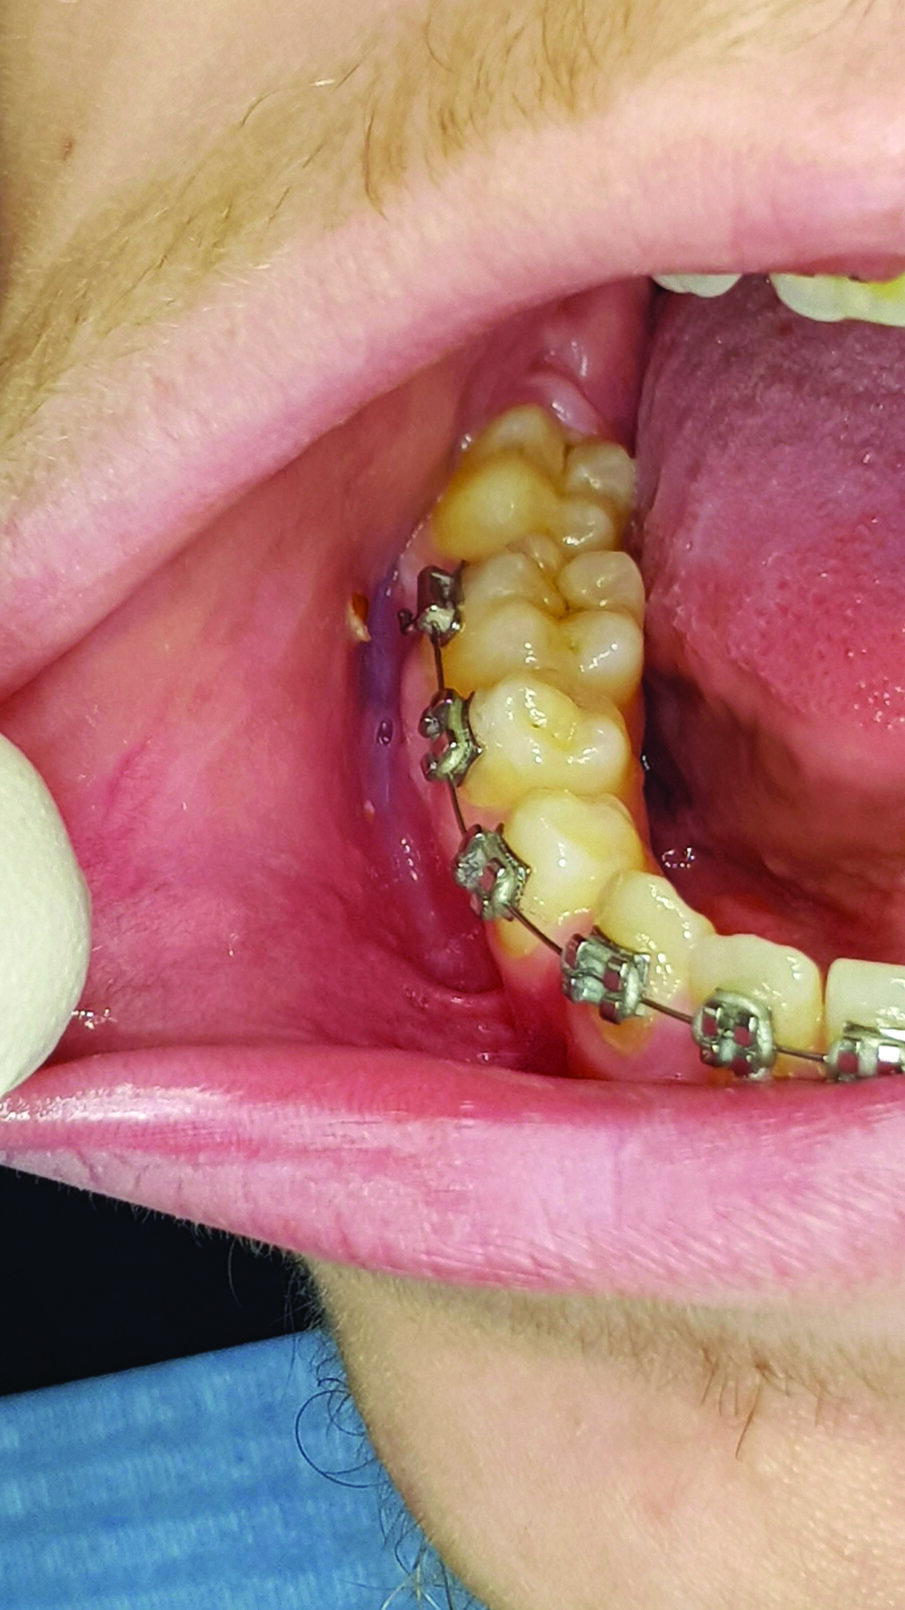

Un paziente maschio di 17 anni, in perfetto stato di salute generale, durante un controllo ortodontico presenta una lesione ulcerativa provocata dallo strofinamento della mucosa buccale con i bracket in corrispondenza del dente n 43-44-45 . Anche in questo caso si prescrive lo stesso collutorio puro per 1 minuto ogni 8 ore per 7 giorni e lo stesso gel orale, descritto precedentemente ogni 8 ore per 7 giorni. Dopo 5 giorni la lesione ulcerativa da strofinamento della mucosa buccale è completamente regredita (Figg. 3, 4).

Fig. 4 - La lesione provocata dallo strofinamento della mucosa buccale con i bracket in corrispondenza degli elementi 43-44-45 è completamente regredita dopo 5 giorni di trattamento.